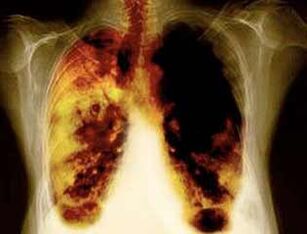

- Reduzieren Sie das Risiko, Lungenkrebs und viele andere Krebsarten zu entwickeln.

- Reduzieren Sie das Risiko, bestimmte Lungenerkrankungen zu entwickeln (z. B. chronisch obstruktive Lungenerkrankungen).

- In der Zeit 2 Wochen bis 3 Monate nach der Ablehnung des Rauchens verbessert sich die Arbeit der Lunge und es steigt die Stärke.

- Nach 1-9 Monaten treten der Husten und der Atemmangel auf: Die Wimpern (kleine Haare) beginnen den Schleim normal zu behandeln, die Lunge zu reinigen und das Infektionsrisiko zu verringern.

- 10 Jahre nach der Beendigung von Rauch von 40%nimmt die Wahrscheinlichkeit von Lungenkrebs um 40%ab.